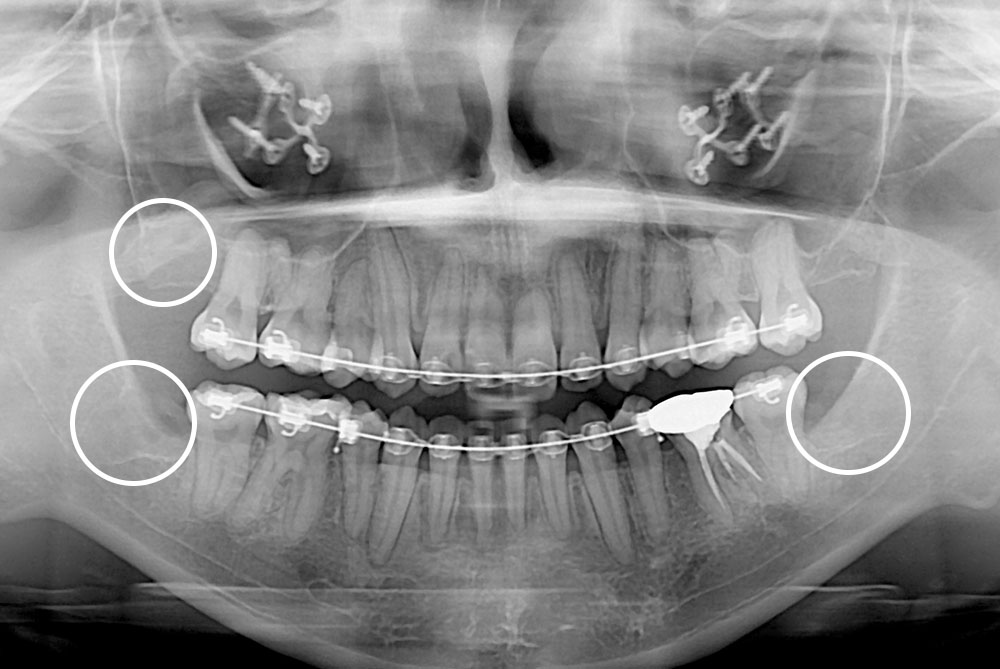

[사랑니] 매복 사랑니 발치

치료후 : 2018-10-15

세종치과는 구강악안면외과학 박사이신 원장님이 발치하는 치과입니다.